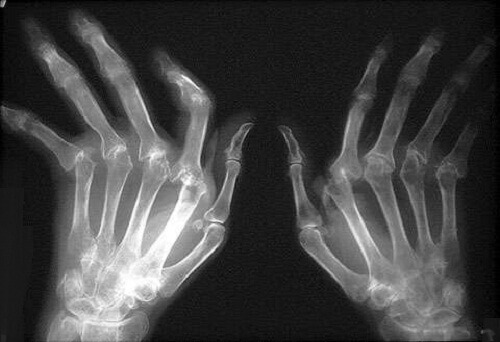

To κύριo και πιο ορατό σύμπτωμα είναι το οίδημα ή η φλεγμονή των αρθρώσεων, η οποία προκαλεί πολύ πόνο. Τα σημεία που πλήττονται περισσότερο από τη ρευματοειδή αρθρίτιδα είναι οι καρποί, οι αγκώνες, οι ώμοι, τα δάχτυλα των χεριών και των ποδιών, τα ισχία, οι αστράγαλοι και τα γόνατα. Είναι σύνηθες για τους ασθενείς που πάσχουν από αυτή την ασθένεια να έχουν την αίσθηση της ακαμψίας, ιδιαίτερα το πρωί όταν ξυπνούν.

Ακόμη, είναι δυνατόν να εμφανιστούν τα λεγόμενα ρευματικά οζίδια. Πρόκειται για εξογκώματα στο δέρμα (ιδιαίτερα στην πλάτη, στα χέρια και στα πόδια) ή μέσα στο σώμα. Στη συνέχεια, η φλεγμονή δίνει τη θέση της στις παραμορφωμένες αρθρώσεις, όταν η νόσος φτάσει σε προχωρημένο στάδιο.